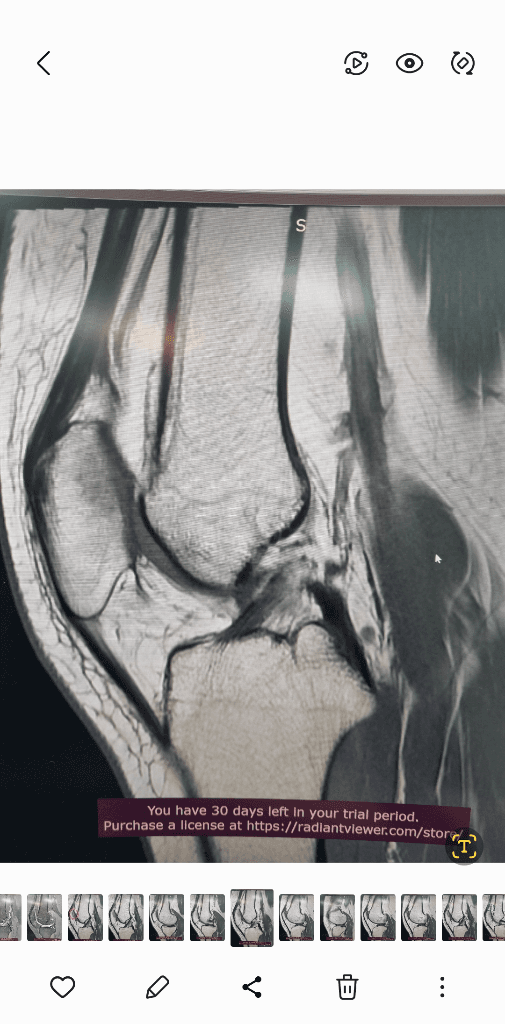

1. 추벽이 아닙니다.

2. 슬개골 관절면에 외상으로 인한 골수부종입니다.

3. 관절면 손상여부는 첨부해주신 영상만으로 알 수 없습니다